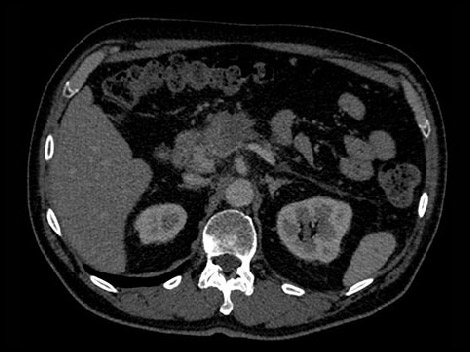

Возраст: 51 Рост: 1,82 м Вес: 79 кг КТ-ангиография брюшной полости при 70-секундной задержке введения контрастного вещества

Возраст: 50 Рост: 1,80 см Вес: 75 кг КТ-ангиография брюшной полости при 70-секундной задержке введения контрастного вещества

В рассматриваемом гипотетическом случае рентгенологам требуется больше информации о подозрительном образовании в поджелудочной железе. Для постановки точного диагноза необходимо определить его материальный состав.

В отличие от стандартных, изображения, полученные с помощью системы IQon Spectral CT, всегда несут спектральную информацию — для этого не требуется планирования специального режима исследования и дополнительных настроек. Таким образом, пользователь может выполнять анализ спектральных данных любого изображения в ретроспективном режиме с помощью различных инструментов просмотра. К примеру, всегда можно выбрать моноэнергетический уровень или вычленить данные о составе тканей. Попробуйте сами.